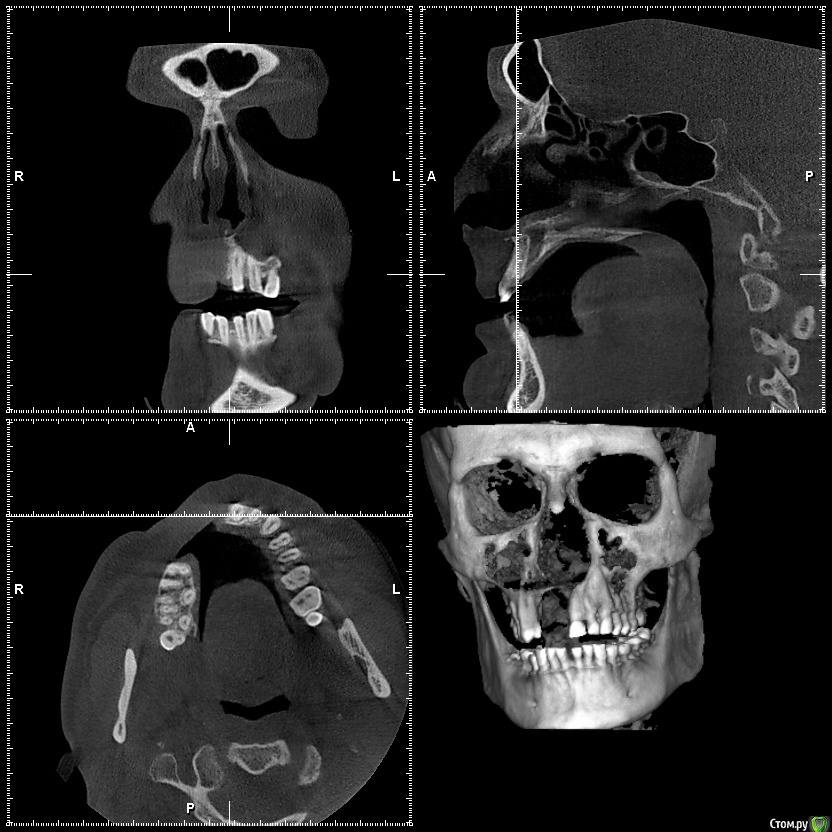

L.E.S.I.K. Опубликовано 13 июля, 2017 Поделиться Опубликовано 13 июля, 2017 Доброго времени суток, коллеги. Пациент обратился с желанием иметь несъемную конструкцию на имплантах. В анамнезе 5 мес назад операция по поводу хронического одонтогенного остеомиелита верхней челюсти. В настоящее время клинический признаков воспаления нет. Есть только значительный дефект. 3 класса по Зиберту. Какие возможны методы аугментации кости в объеме необходимом для имплантации? Мне на ум приходит только блоки из подвздошной Ссылка на комментарий

Bier Опубликовано 13 июля, 2017 Поделиться Опубликовано 13 июля, 2017 плохие очень снимки, толком ничего не понятно. Блоки с подвздошки забудьте, они резорбируются быстро. Тут нужен один из вариантов GBR Покажите нормальные срезы, чтобы был ясен уровень костных пиков на соседних зубах. Ссылка на комментарий

L.E.S.I.K. Опубликовано 13 июля, 2017 Автор Поделиться Опубликовано 13 июля, 2017 Возле 21 пик есть, а в обл 25 снижен, корень оголен на четверть. Смущает также отсутствие местами костно дна полости носа Ссылка на комментарий

Maxfac Опубликовано 13 июля, 2017 Поделиться Опубликовано 13 июля, 2017 Только реваскуляризированный лоскут. По анатомии дефекта подойдёт бедренный. Какова причина остеомиелита? Что с общей соматикой? Сколько лет? Ссылка на комментарий